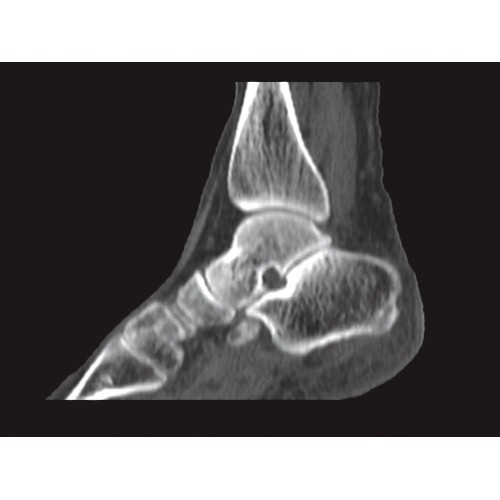

Специализированные исследования

Обеспечивает высокую точность при кардиологических исследованиях, визуализации костных структур и суставов. Подходит для динамического наблюдения в ходе лечения.